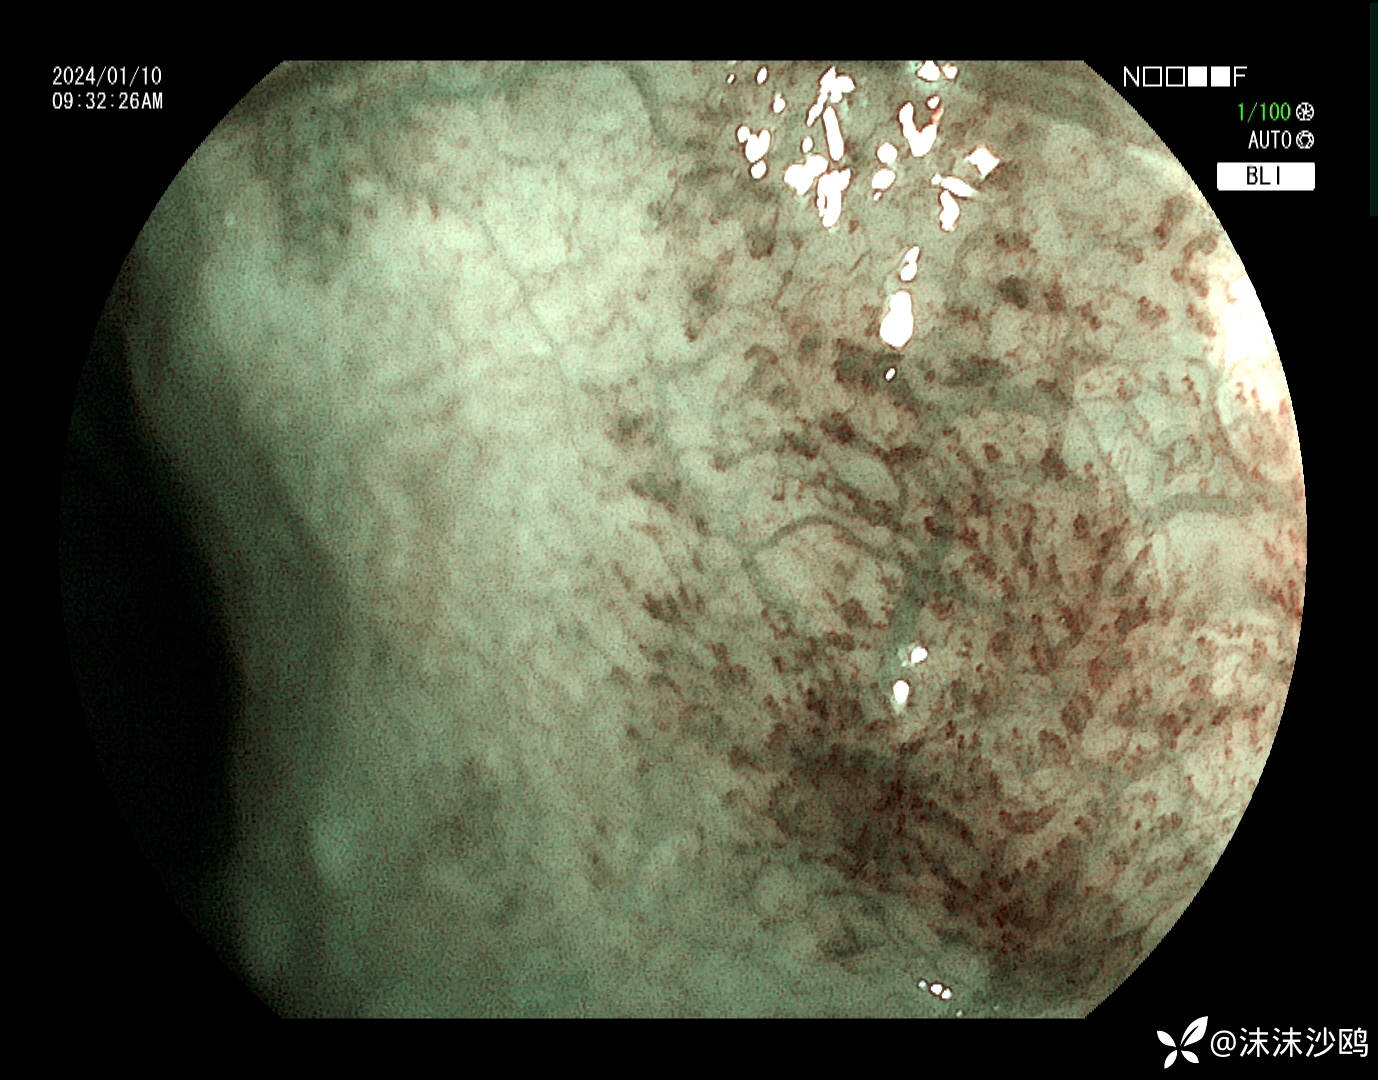

中年男子,自21年年初胃镜发现食管粘膜发红,今天是第五次复查胃镜。就是距门齿35cm一片状粘膜发红,表面比较平坦光滑,茶褐色改变。

今天的,做了放大,但我们没有碘染色剂,所有没做碘染。

后三次都是我做的,因为今天对比了病灶,感觉变化不明显,没有取病检。

想问,单纯的慢性炎,能解释这片存在了这么长时间的粘膜发红吗?蹲大佬解析。